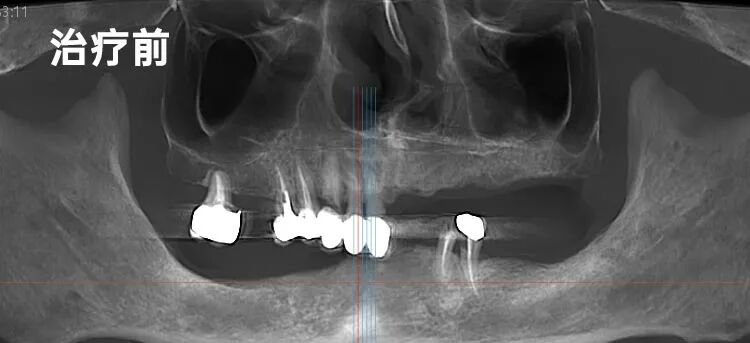

谭先生的口腔情况,是一道叠加了心理恐惧的医学难题。

经李院长详细检查,问题远比想象复杂:全口余牙需拔除,而下颌后牙区的骨高度严重不足——“就像想在沙滩上盖高楼,地基却不够深。”这对种植而言是巨大挑战。更棘手的是,谭先生对看牙有着根深蒂固的恐惧,复杂的病情让他多年裹足不前。

如何在不理想的“地基”上,为他重建一口能安心吃饭的牙,同时确保漫长治疗过程舒适无痛,彻底化解他的心魔?这道双重难题,摆在了李院长面前。